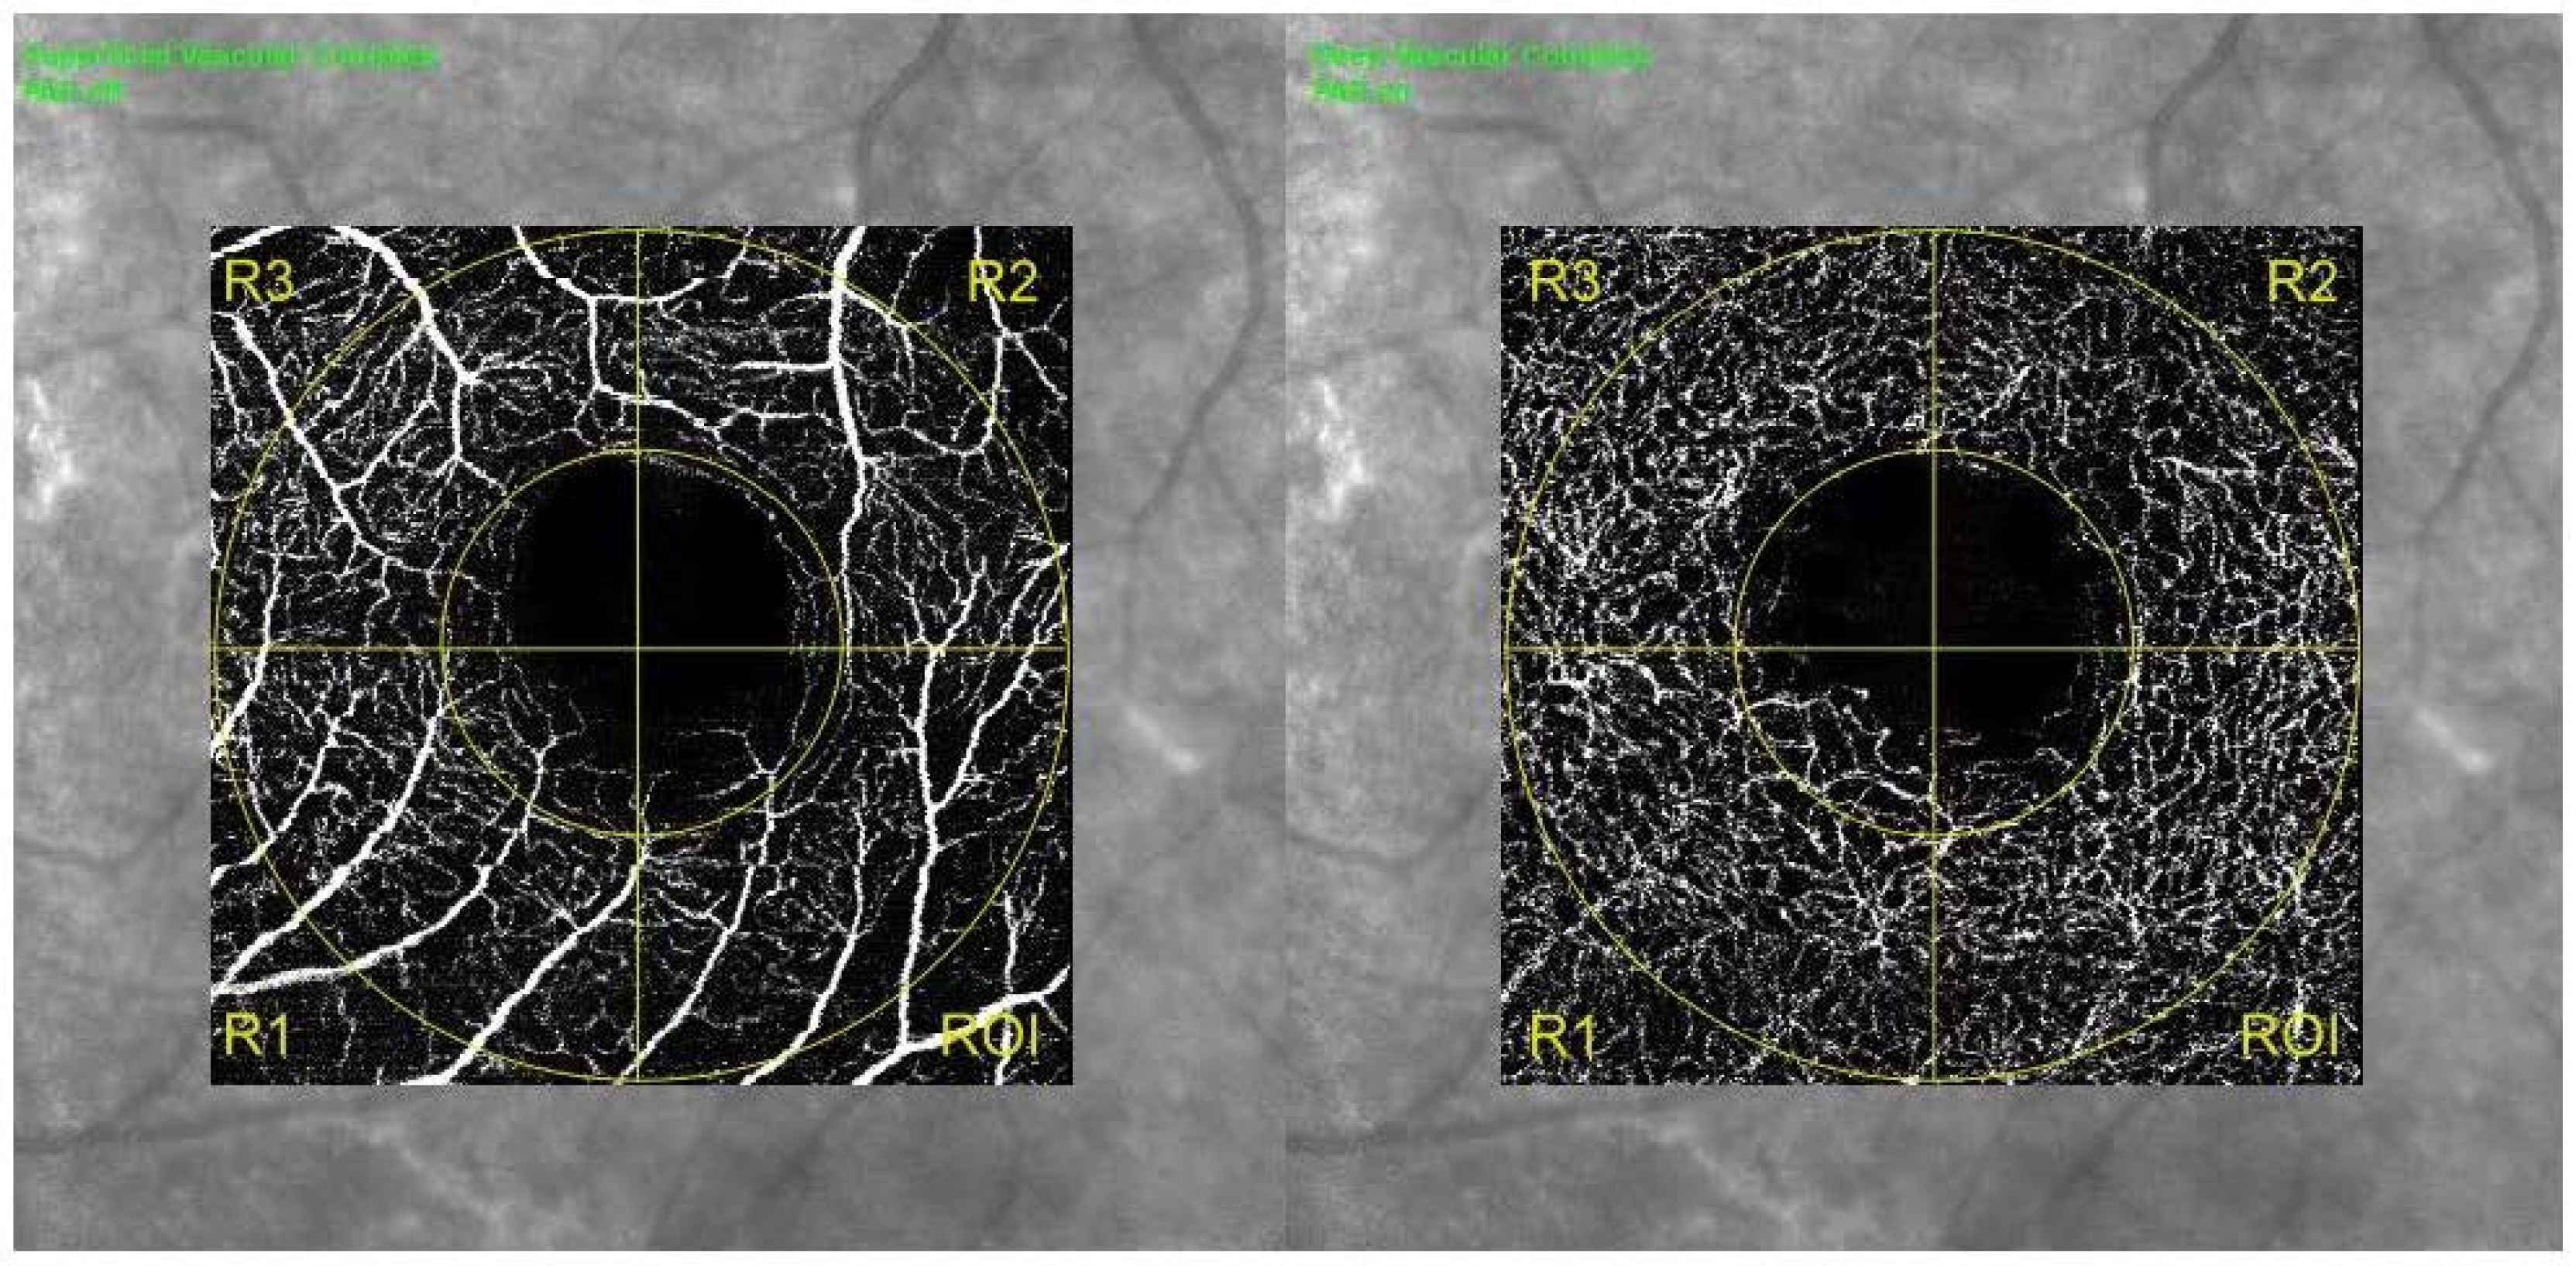

| DCP | CFZ circularity | 0.55 (0.09) | 0.62 (0.07) | 0.003 |

| CFZ area (mm2) | 0.47 (0.18) | 0.43 (0.12) | 0.055 | |

| CFZ perimeter (mm) | 3.27 (0.22) | 2.95 (0.27) | 0.067 | |

| Foveal VD (%) | 19.21 ± 1.34 | 22.13 ± 1.59 | 0.087 | |

| Foveal PD (%) | 15.82 ± 1.69 | 20.10 ± 1.44 | 0.021 | |

| Parafoveal VD (%) | 0.47 ± 2.87 | 0.49 ± 2.52 | 0.147 | |

| Parafoveal PD (%) | 0.36 ± 2.11 | 0.45 ± 2.32 | 0.005 |